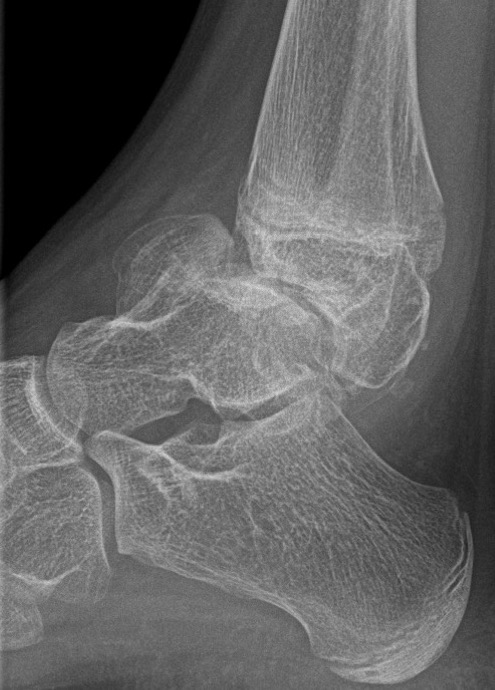

Ankle

- valgus

- fibular shortening with valgus distal tibia

- wedge-shaped distal tibial epiphysis

- leads to valgus talar tilt in abnormal mortise